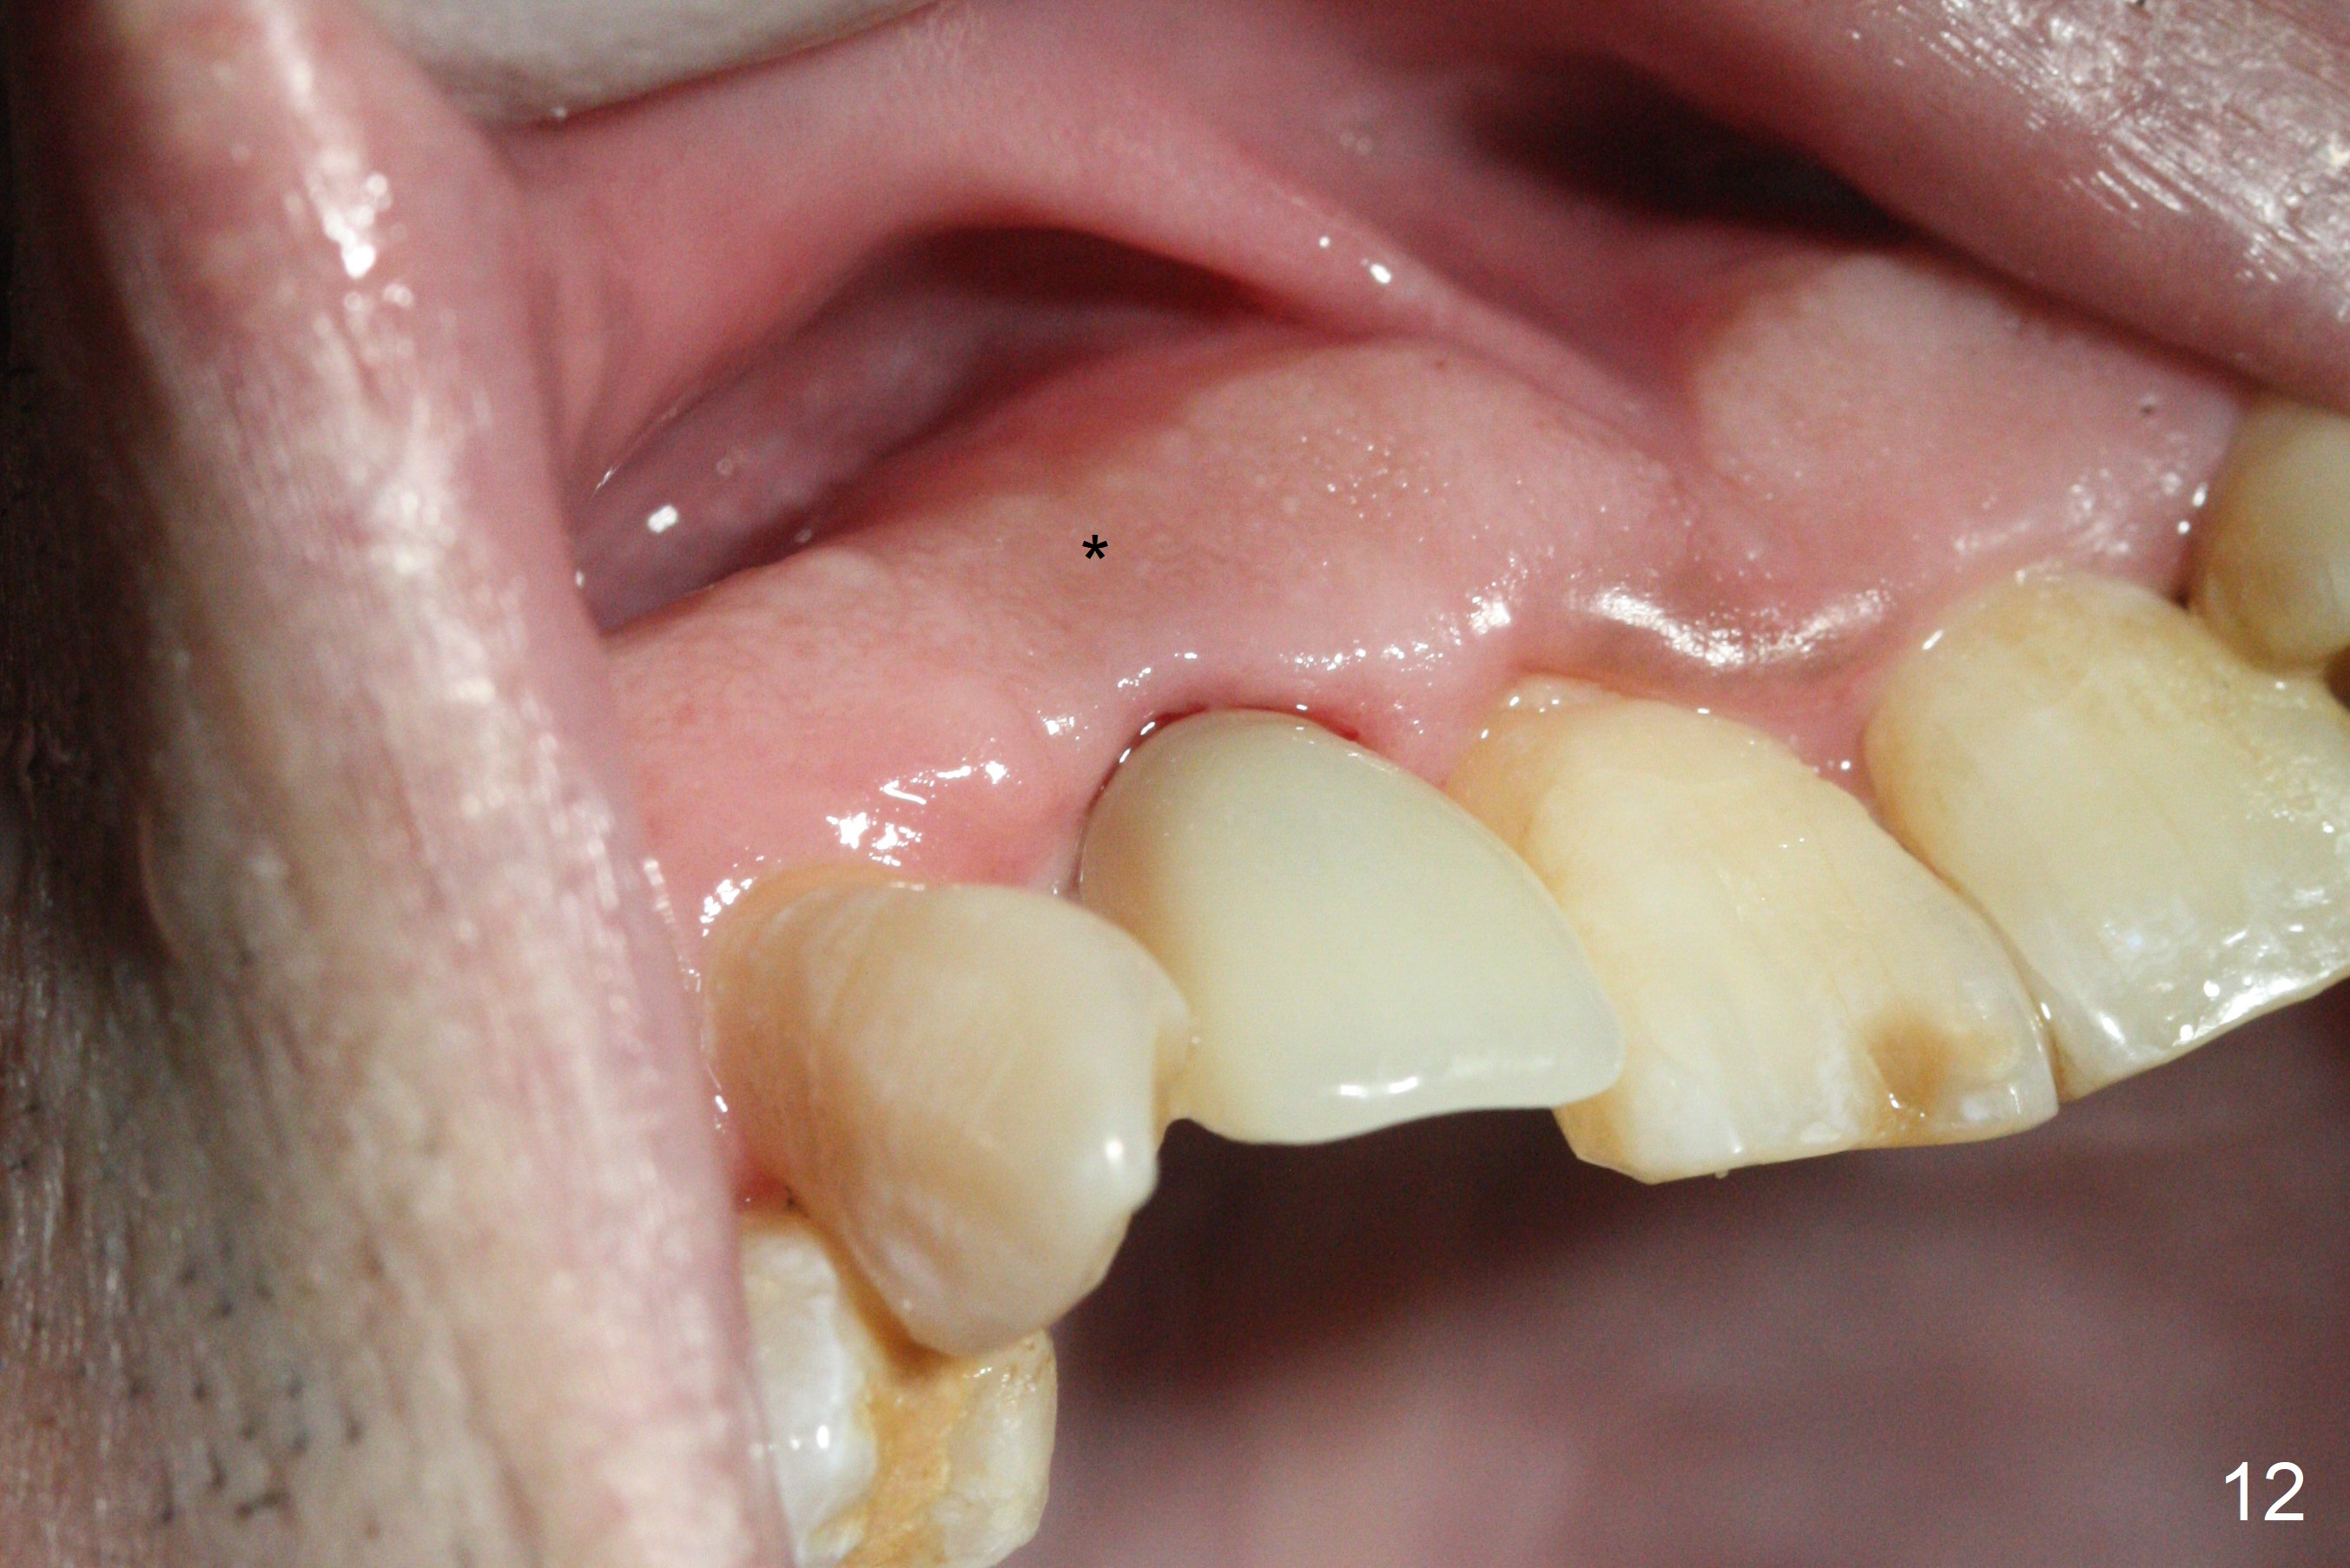

Sixteen days postop, the patient is doing fine, although the labial fistula has not disappeared (Fig.8 <). The detached distolabial papilla is healing (Fig.9 *) with mild bone graft exposure (^). The lacerated distopalatal papilla is also healing (Fig.10 *). These complications are related to flap surgery. The apical portion of the socket appears to have reduced 4 months postop (Fig.14). When the definitive restoration is delivered 5 months postop, there is gingival recession, including the distal of #8 (Fig.11 arrows, which is expected to improve over time) due to flap surgery. The labial plate collapse is minimal (Fig.12 *), while the palatal laceration (Fig.10) has healed (Fig.13). When the patient returns 1.5 years post cementation, there is increased bone density next to the coronal portion of the implant, equivalent to the bone graft (Fig.15 *). The fistula is absent (Fig.16). The crestal bone loss remains 2.5 years post cementation (Fig.17 *), although there is no sign of periimplantitis (magnification). Oral hygiene is poor. There is no change in the soft (gingival recession; data not shown) or hard tissues 3 years 8 months post cementation (Fig.18).